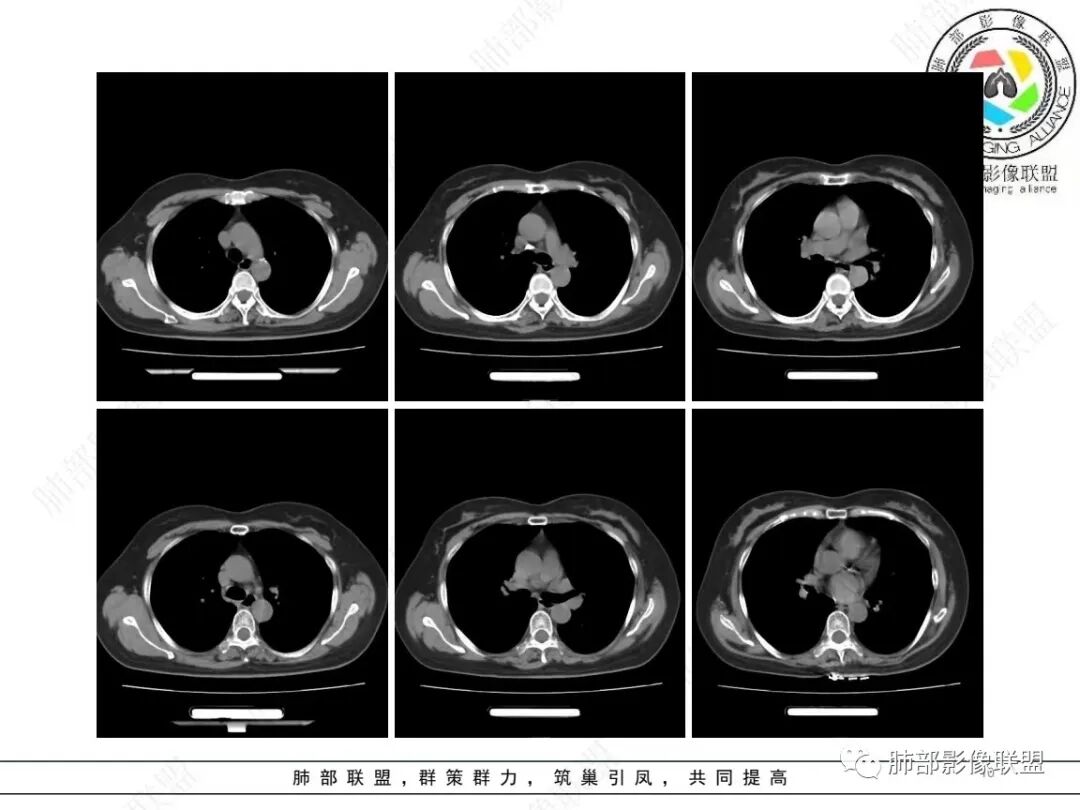

这个病例从病史方面看是体检发现的,而且她的炎症指标都不高,那么我们临床上这种体检发现的肺部的这种结节性病变,肯定会考虑是感染还是肿瘤,这种情况下,一般情况下,我喜欢收住院,然后一边抗感染,一边进行辅助检查,那么,感染性的考虑肉芽肿性炎。,结核,真菌,特别是隐球菌,可能要放在首位,因为这个病灶周边有晕,而且在胸膜下,结节看上去好像是多个结节聚集融合形成的。所以住院之后很可能就进行结核,隐球,真菌等方面检查,再就是肿瘤方面的检查肯定也进行了,短期抗炎治疗进行复查,复查之后那么这个病灶有没有变化?怎么样变化的,为下一步可能就提供方向了。大部分病号的心理素质并不是那么高,所以说很多病号加上医生就选择了手术这个方法了,因为手术除了诊断之外,它还可以直接进行治疗,到底是李鬼还是李逵?切完之后送病理,一切就真相大白了,那么,从这个胸部CT片的表现看的话,右下肺的这么偏实性的结节,周边有晕。而且病灶收缩为主,就像一种兵器月牙铲,周边应该是有血管集束症的。病灶的中间好多那种蜂窝状的支气管的那种扩张应该是。好像还有一点胸膜凹陷征。从这些征像上来看的话,恶性的可能性比较大,具体是腺癌啊,还是别的什么肿瘤?单纯从影像学上来说的话,很难去确定。所以我觉得给一个临床的大致方向,然后进一步去检查治疗,可能就可以了。

1、临床特点:58岁女性,体检发现右肺结节7天,无基础病,中性粒细胞百分比略高,无实验室检查无特殊。

2、影像特点:右肺下叶胸膜下不规则结节,矢状位整体病灶沿着支气管方向呈斑片状,不均匀强化。病灶边缘多平直、凹陷(从部分层面可见极其像月牙铲),缺乏膨隆感,周围可见多发长索条影,病灶内可见多发充气支气管影,大部分支气管完全贯通病灶并轻度扩张,极少支气管进入病灶内堵塞,观察横断位视频、部分层面病灶周围可见边界欠清的ggo。纵隔窗病灶内未见明显钙化影。未见卫星病灶及树芽征。

3、综合分析:中老年女性胸膜下不规则结节,无特殊临床表现,实验室检查亦无特殊,病灶在部分断面呈斑片状,边缘多平直甚至凹陷,缺乏分叶及膨隆感,未见粗短毛刺及胸膜凹陷,部分层面似见”月牙铲“样外形,但缺乏张力的“月牙铲”不太可靠。灶周磨玻璃晕也会让人警惕肺腺癌可能,磨玻璃影边界是否清晰常须薄层仔细分辨。

实性密度为主结节影,支气管密切相关,边缘多平直,缺乏分叶膨隆感,缺乏张力,有磨玻璃晕但边界不清。更符合慢性炎性病变。

病理提示隐球菌感染可能。肺部隐球菌感染孤立性病灶与肺腺癌的鉴别诊断是个永恒的话题。